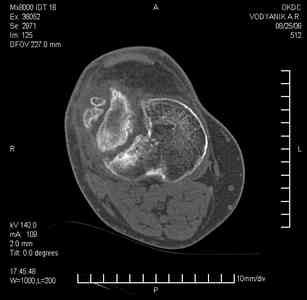

Тугой ложный сустав правого бедра в сочетании неправильно сросшимся переломом большеберцовой кости

В 2002 v внутрисуставной оскольчатый перелом проксимального метаэпифиза правой большеберцовой кости; в 2005 v внутрисуставной оскольчатый перелом дистального метаэпифиза правой бедренной кости.

В обоих случаях в разных лечебных учреждениях проводилось оперативное лечение переломов. При осмотре в отделении на основании результатов клинического осмотра и данных визуальных методов обследования поставлен диагноз: тугой ложный сустав дистальной трети правой бедренной кости, состояние после накостного остеосинтеза перелома типа 33-В2.2 ; несросшийся перелом надколенника; неправильно сросшийся перелом латерального мыщелка правой большеберцовой кости, состояние после металлоостеосинтеза перелома 41-В2.2; сочетанная осевая деформация правой ноги: варусная деформация правого бедра, вальгусная деформация правой голени; посттравматический артроз коленного сустава 4 ст по Kellgren-Lowrence; выраженное нарушение функции ходьбы и опоры.

Внешний вид ноги больного, данные рентгенографического обследования и избирательно выделенные компьютерные томограммы приведены в приложении. В именах КТ использовано кодирование уровня по АО, т.е. _41, например, означает проксимальную треть голени. В отделении намечен v очень предварительно v следующий план лечения: